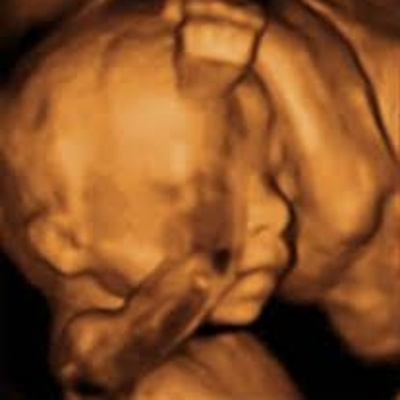

En este programa nos centramos en la ecografía más importante del embarazo: la de la semana 20. En esta prueba conoceremos el sexo de nuestra bebé y sabremos si todo marcha bien. Nuestra ginecóloga y nuestra psicóloga nos contarán como afrontar este momento. Además os desvelaremos el origen de las ecografías y entrevistaremos a la responsable de un centro especializado en ecografías en 4D. También os traemos un mami consejo, un ejercicio para manteneros en forma en el embarazo, música y, por supuesto, las respuestas a las preguntas que cada semana nos enviais al consultorio.